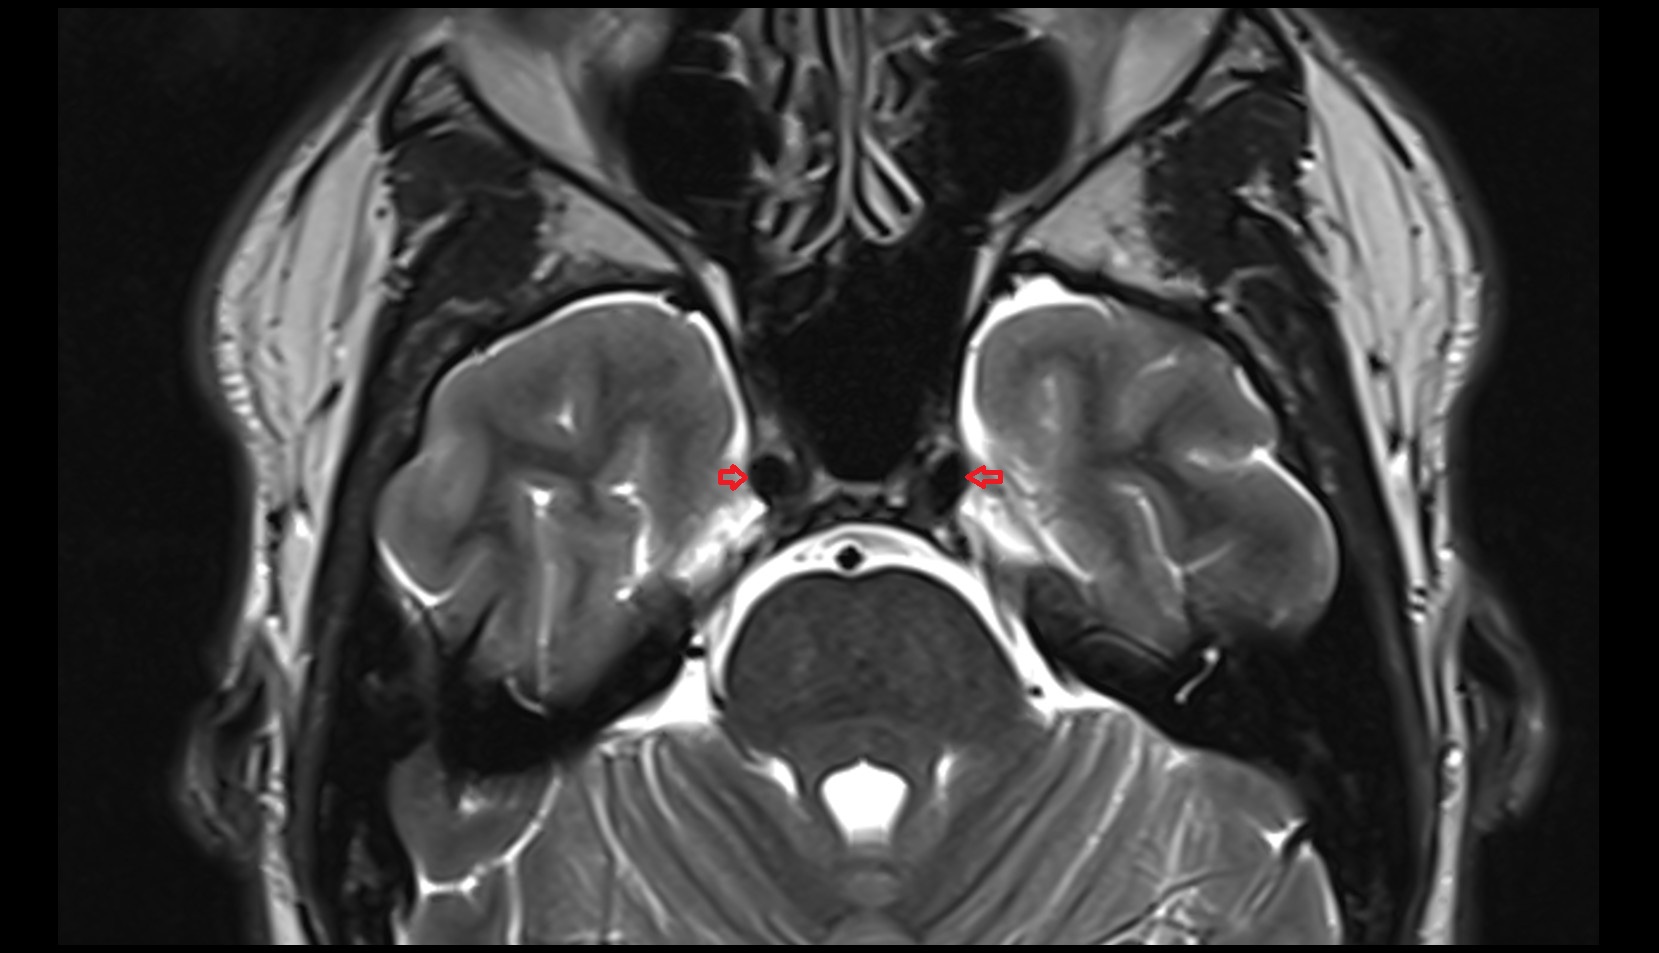

- Hippocampus